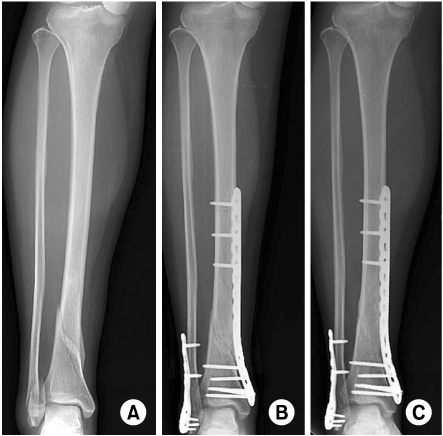

Эта блокирующая пластина дистального отдела малоберцовой кости является наиболее часто используемой хирургами анатомической пластиной при хирургическом лечении переломов латеральной лодыжки.

Фиксирующая пластина дистального отдела малоберцовой кости имеет контур, соответствующий естественной анатомии дистального отдела малоберцовой кости, что может эффективно уменьшить повреждение и раздражение мягких тканей.

После вправления перелома в операционной к наружной поверхности малоберцовой кости прикрепляют стопорную пластину дистального отдела малоберцовой кости и привинчивают к кости. Пластина помогает поддерживать анатомическую репозицию перелома, позволяя

организму с течением времени срастаться с костью. Их низкопрофильная конструкция сводит к минимуму раздражение мягких тканей, но достаточно прочна, чтобы стабилизировать переломы.

Дистальная блокирующая пластина малоберцовой кости доступна из титанового материала (TC4, чистый титан). Головка фиксирующей пластины дистального отдела малоберцовой кости LCP имеет 4 круглых резьбовых отверстия для блокировки, она принимает стопорный винт 3,5 мм и кортикальные винты. Низкопрофильная конструкция эффективно снижает повреждение мягких тканей, способствует быстрому восстановлению кости.

Стержень пластины имеет диапазон от 3 до 8 отверстий LCP для фиксации сломанной кости различной длины, комбинированные отверстия с конструкцией блокировки и сжатия могут принимать стопорные винты 3,5 мм и кортикальные винты 3,5 мм. Отверстие в валу облегчает первоначальное позиционирование пластины.